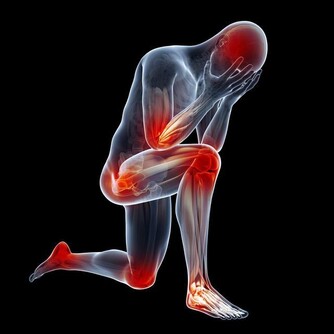

黑木耳富含的多糖膠體有良好的清肺功能,

對霧霾天氣吸入的有害雜質有很強的吸附作用,

可以緩解再霧霾天天吸入污濁空氣引起的咽部瘙癢,

霧霾天晚上吃點木耳做的菜非常有必要!